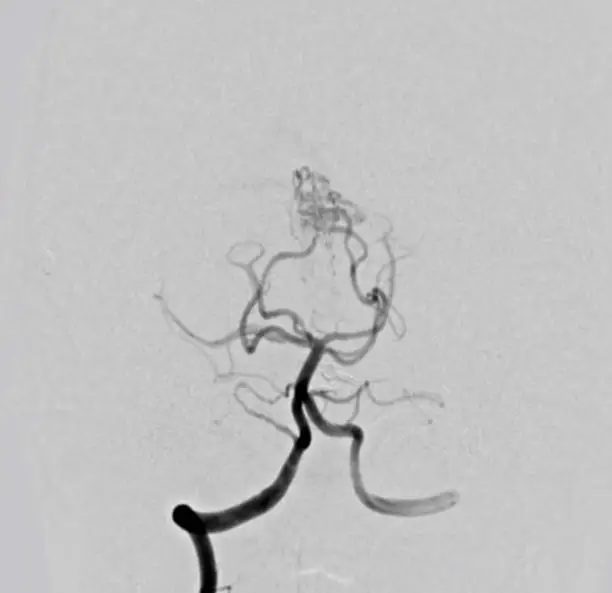

해면상 혈관종의 진단은 주로 임상적인 관찰을 통해 이루어집니다. 의사는 환자의 병력을 조사하고 종양의 모양과 크기, 촉감을 확인하여 해면상 혈관종인지 여부를 판단합니다. 필요에 따라 초음파나 MRI와 같은 영상 검사를 통해 혈관종의 정확한 위치와 크기, 주변 조직과의 관계를 확인할 수 있습니다. 특히, 내부 장기에 발생한 혈관종은 이러한 영상 검사를 통해 더욱 정확하게 평가됩니다.

해면상 혈관종이 뇌나 척수 등 중요한 부위에 위치한 경우, 신경학적 검사를 통해 종양이 신경계에 미치는 영향을 평가할 수 있습니다. 이때 신경학적 검사는 환자의 운동 기능이나 감각, 반사 작용 등을 점검하여 혈관종의 크기와 위치가 신경계에 미치는 영향을 파악하는 데 도움을 줍니다.